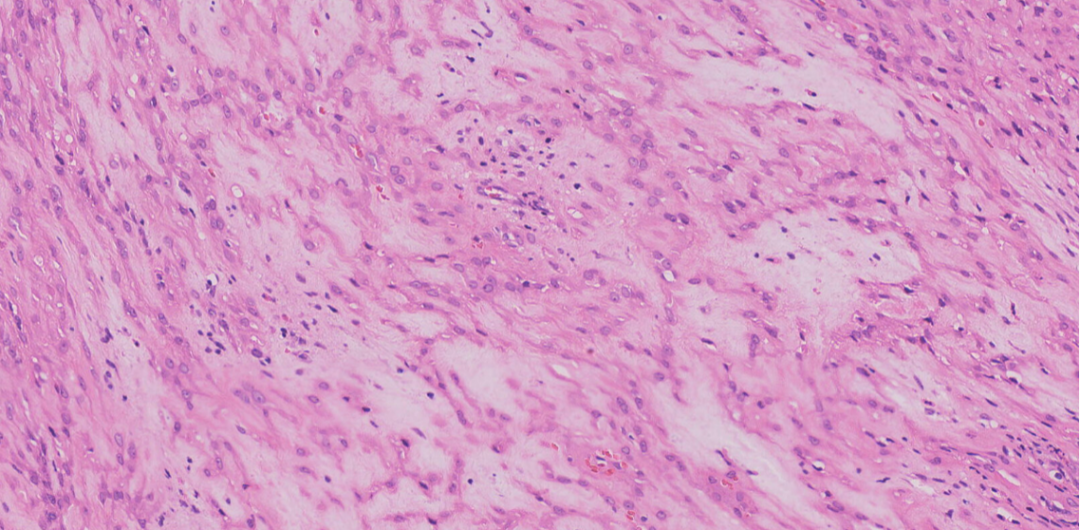

中倍镜下肿瘤结构呈丛状,条索状生长,间质黏液变性

肿瘤呈丛状,条索状生长,间质黏液变性

细胞温和,圆形、多边形,胞浆丰富,嗜酸性,可见核仁

偶见核分裂